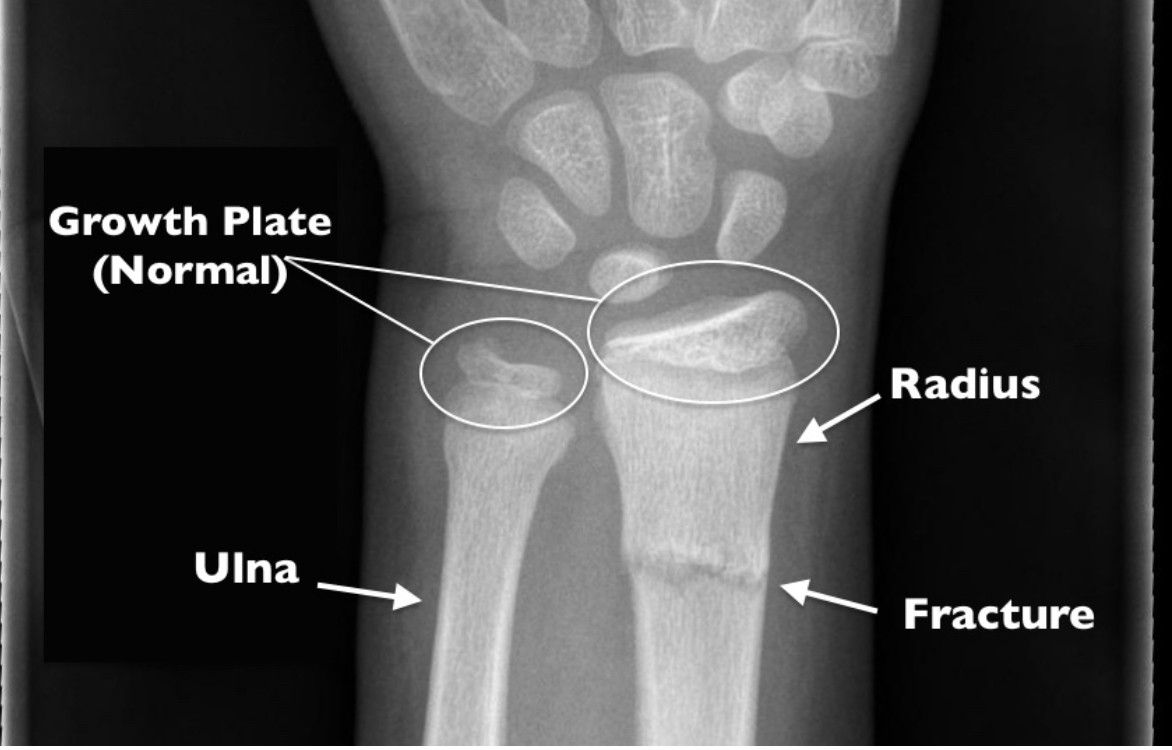

Fraktur Radius

Fraktur radius adalah istilah medis yang digunakan ketika terjadi patah tulang pada bagian radius.